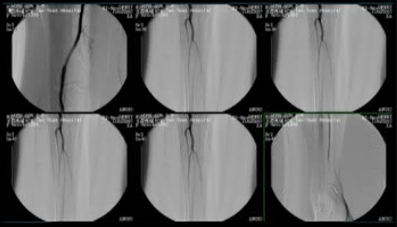

黑色的那个是血管,从大腿流到中间那个图片,就是膝盖的部分,这个血管还看得到。

膝盖有半月板,那里黑色的一条流下来,这个就是血管,血管显影,那这个都还没有问题,我们看下一张。

你看右侧那一面也是,小腿,到黑色的它已经流不下来,那到脚踝的部分更是一片苍白,所以可以确定黑脚阿妈脚趾头黑掉,从小腿以下的血管就流不下来了。